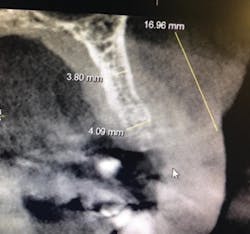

Figure 8: Pre-op CT scan

A 50-year-old female presented with a missing tooth No. 12 that was extracted for unknown reasons more than 10 years ago (figure 7). The patient was referred to our office for an implant consultation. Upon review of a CT scan, it was revealed that at the widest area buccal-lingually there was 4.09 mm and at the narrowest 3.8 mm (figure 8). She was presented with two treatment options: bone grafting or a narrow-diameter implant. She opted for the narrow-diameter implant, as it eased several of her concerns: she was unhappy with a removable appliance, worried about a block graft for a single tooth, and finances were a burden.